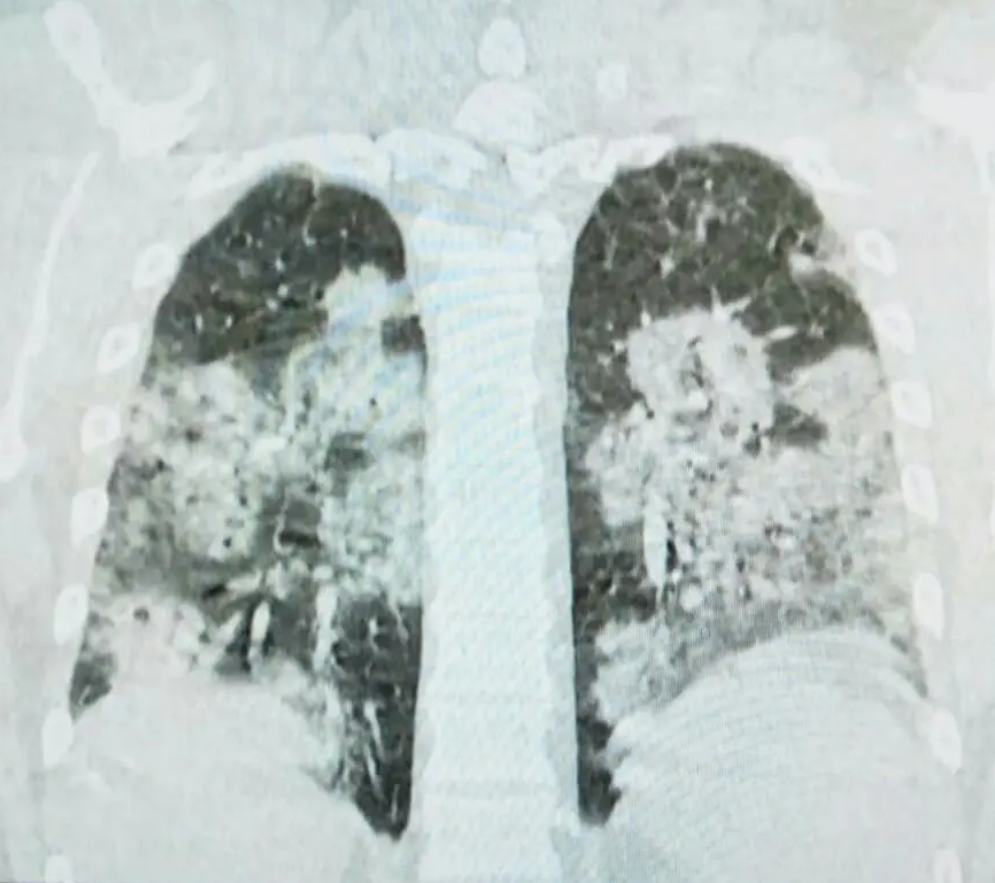

Doktor Stevanović na svom Facebook profilu objavio je CT pluća jednog od pacijenata, mladog čovjeka koji je nepušač i koji je bio zdrav prije infekcije koronavirusom.

“Za one koji ne znaju, zdrav je crni dio pluća. Doktori, neznalice, peta kolona, diktatori itd. posegnuli su za slamku spasa i ordinirali lijek koji je pacijent kupio. Oporavlja se”, poručio je doktor Stevanović i dodao:

“Lijek je skup i ne može se nabaviti na teret zdravstvenog osiguranja. I svi ostali hospitalizirani bolesnici imaju upalu pluća. Nadati se da će što manje njih imati ovako tešku. I vi, dragi sugrađani, možete pomoći da što manje naših građana oboli.”